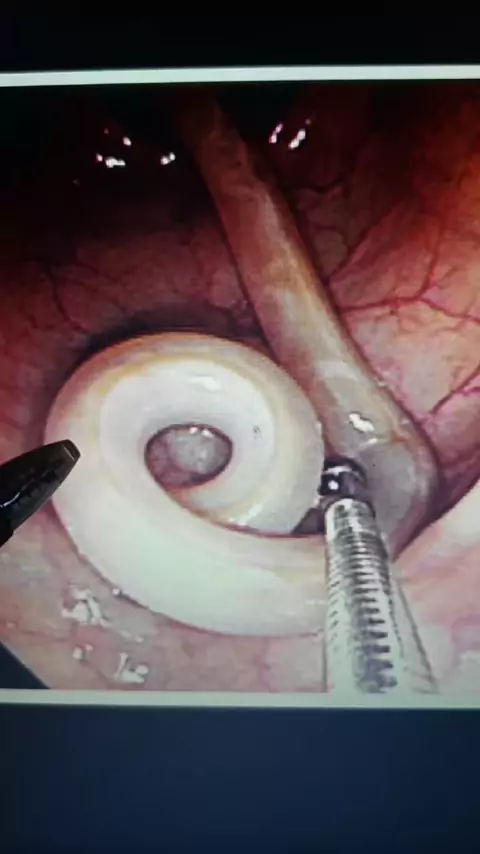

Membalas @reres936 beberapa kondisi yang mengharuskan kita untuk operasi sesar #operasisesar #sc #indikasisc #penyebabsc #operasimelahirkan #infokesehatan #obgyn